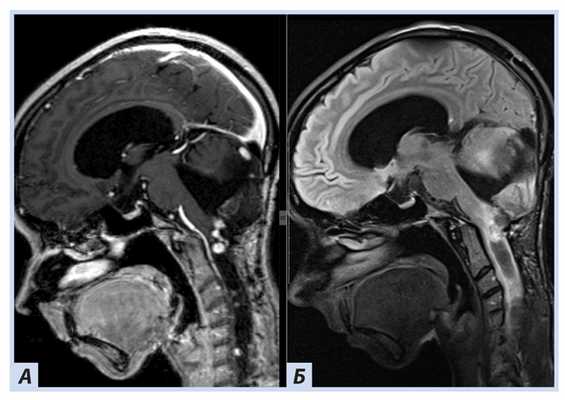

Лучевые методы. На МРТ-изображениях головного мозга выявлено характерное двустороннее поражение глаз (рис. 1), по данным КТ — с участками обызвествления (рис. 2). Также на КТ головного мозга были выявлены зона послеоперационных кистозно-глиозных изменений с наличием кисты и узла на уровне посттрепанационного дефекта в правом полушарии мозжечка, а также аналогичные зоны дорзальнее и в субкортикальных отделах; в левой гемисфере мозжечка определялись кистозные изменения (рис. 3).

Рис. 1. Пациентка П., 30 лет, с диагнозом «Болезнь Гиппеля−Линдау»: магнитно-резонансная томография головного мозга

Примечание. А, Б — Т2- и Т1-взвешенные изображения. В полости правой глазницы объемное образование с неоднородным МР-сигналом; В — постконтрастное Т1-взвешенное изображение, режим подавления сигнала от жира: определяется интенсивное, но гетерогенное контрастирование образования. Кровоизлияние в сетчатку справа.

Рис. 3. Пациентка П., 30 лет, с диагнозом «Болезнь Гиппеля−Линдау»: магнитно-резонансная томография головного мозга

Примечание. А — Tirm-режим: на фоне кист мозжечка визуализируется мягкотканный компонент, прилегающий к кисте справа; Б — DWI-режим: зона рестрикции диффузии по ходу стенки кисты справа; В — постконтрастное Т1-взвешенное изображение, режим подавления сигнала от жира: в той же зоне отмечается накопление.

В спинном мозге больной на уровне шейного отдела были выявлены кистозные полости с узлами гемангиобластом (рис. 4).

Рис. 4. Пациентка П., 30 лет, с диагнозом «Болезнь Гиппеля−Линдау»: магнитно-резонансная томография спинного мозга

Примечание. А — постконтрастное Т1-взвешенное изображение, режим подавления сигнала от жира: отмечается узел (гемангиобластомы) с аккумуляцией гадолинийсодержащего контраста; Б — Tirm-режим: на фоне кист спинного мозга визуализируется мягкотканный компонент, краниально прилегающий к кисте.